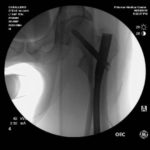

Vor ein paar Stunden wurde Steve deswegen im Palomar Medical Center Escondido operiert. Wie er selber berichtet, ist bei der OP an seinem Spiralbruch, linker Oberschenkel, alles perfekt abgelaufen.

An den Fotos unten kann man gut erkennen, dass der Knochen nun durch ein Titanstück und zwei Schrauben zusammengehalten wird. Den Moment des Sturzes hat Caballero auf Instagram hochgeladen. Den Clip findet ihr unter den Fotos.